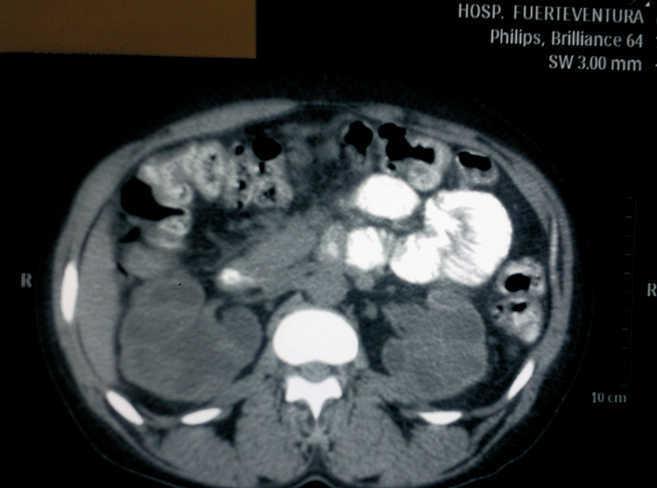

We present the case of a female patient, 41 years of age, with no significant past medical history, who was sent from the emergency department due to deterioration of renal function with serum creatinine (SCr) of 6.5mg/dl, in the setting of vaginal bleeding requiring transfusions. At that time, she was diagnosed with uterine fibroids by the gynaecology service. She was admitted for further work-up and a renal ultrasound was performed, showing grade IV bilateral hydronephrosis, with poor corticomedullary differentiation, but without visible ureters, for which a CT scan was performed. The CT showed grade IV bilateral ureterohydronephrosis secondary to extrinsic compression by the myomatous uterus, which measured 13 x 9cm (Figures 1 and 2). The urology service was notified, which placed a double “J” catheter in the right ureter, but was unable to place one in the left ureter. Evaluation by the gynaecology service was requested, which postponed a simple hysterectomy to the following week.

Figure 2. Lower CT cut where bilateral ureteral dilatation can be seen.